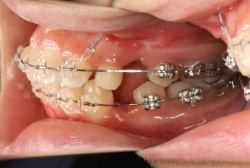

牽引(埋伏犬歯を牽引した症例)

埋伏歯とは、骨または歯茎の下に埋まって出てこない状態の歯のことを言います。埋伏歯があると歯が押されて歯並びが悪くなってしまったり、永久歯が生えてこれない原因になる恐れがあります。

「乳歯が生え替わらない」という主訴で来院したケースです。 診断の結果、「左上永久犬歯が第一小臼歯後方上部に埋伏しているため、左上乳犬歯が晩期残存している症例」と判明しました。

このような症状の場合は、手術で埋伏している永久歯に金具を取り付け、矯正装置で牽引する必要があります。同時に凸凹の解消と前突した前歯を内側に入れるために上下左右の小臼歯を抜歯させて頂くことといたしました。

この方の場合は、マルチブラケット装置にて治療を開始し、治療期間2年3ヶ月で終了しました。犬歯の牽引距離が非常に大きかったため当院の平均治療期間よりも大幅に期間がかかりましたが、埋伏犬歯を完全に正しい位置まで誘導することができました。同時に 前歯の前突と配列の凸凹も解消しました。

このような症例は、成人してしまうと埋伏歯の反応性が悪く、あまりにも動きが悪い場合は牽引をあきらめて抜歯する場合もあります。歯科医院の検診で親知らず以外の埋伏歯を指摘された場合は、できるだけ早く矯正専門医に御相談下さい。

マルチブラケット装置は、装置装着時より数日から2週間程度強い不快感疼痛が有りますが、本症例場合は埋伏歯を開窓手術し、遠く離れた位置に矯正器具が付いていますので強い違和感が生じ、歯ブラシも届きにくく口腔衛生状態を保つのにはかなりの努力が必要です。条件の悪い場所に接着されているため、装置が外れやすく日常生活上もかなり配慮が必要となります。

また、埋伏歯は移動距離が大きくなることが多く、歯根吸収のリスクが高まりますので、移動と休止にゆとりのある治療間隔が必要です。